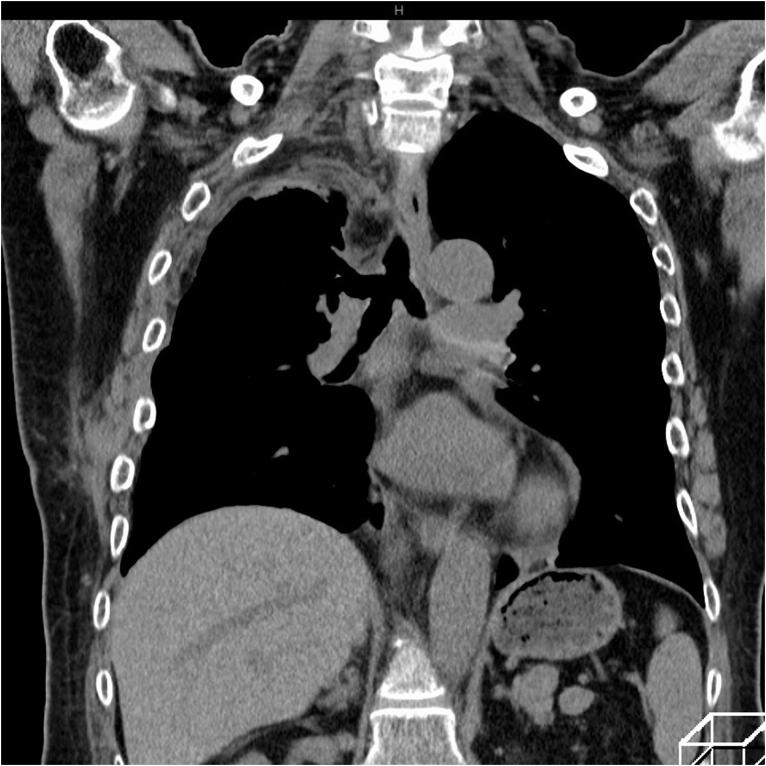

A 69-year-old woman presented to the emergency department with symptoms of worsening dyspnea and subsequent loss of consciousness. She had a history of progressively worsening wheezing and stridor over the course of 2-years and had been diagnosed with asthma. Arterial blood gas sample analysis indicated type II respiratory failure. A chest computed tomographic scan revealed a tumor in the trachea, which was almost completely obstructing the lower tracheal lumen. The tumor was located just above the carina. To alleviate airway constriction and achieve complete resection, carinal resection with reconstruction was performed. The postoperative diagnosis was pleomorphic adenoma of the trachea.

一名69岁女性因呼吸困难加重及随后的意识丧失就诊于急诊科。她有2年逐渐加重的喘息和喘鸣病史,曾被诊断为哮喘。动脉血气样本分析显示II型呼吸衰竭。胸部计算机断层扫描显示气管内有一肿瘤,几乎完全阻塞了气管下段管腔。肿瘤位于隆突上方。为缓解气道狭窄并实现完整切除,实施了隆突切除重建术。术后诊断为气管多形性腺瘤。